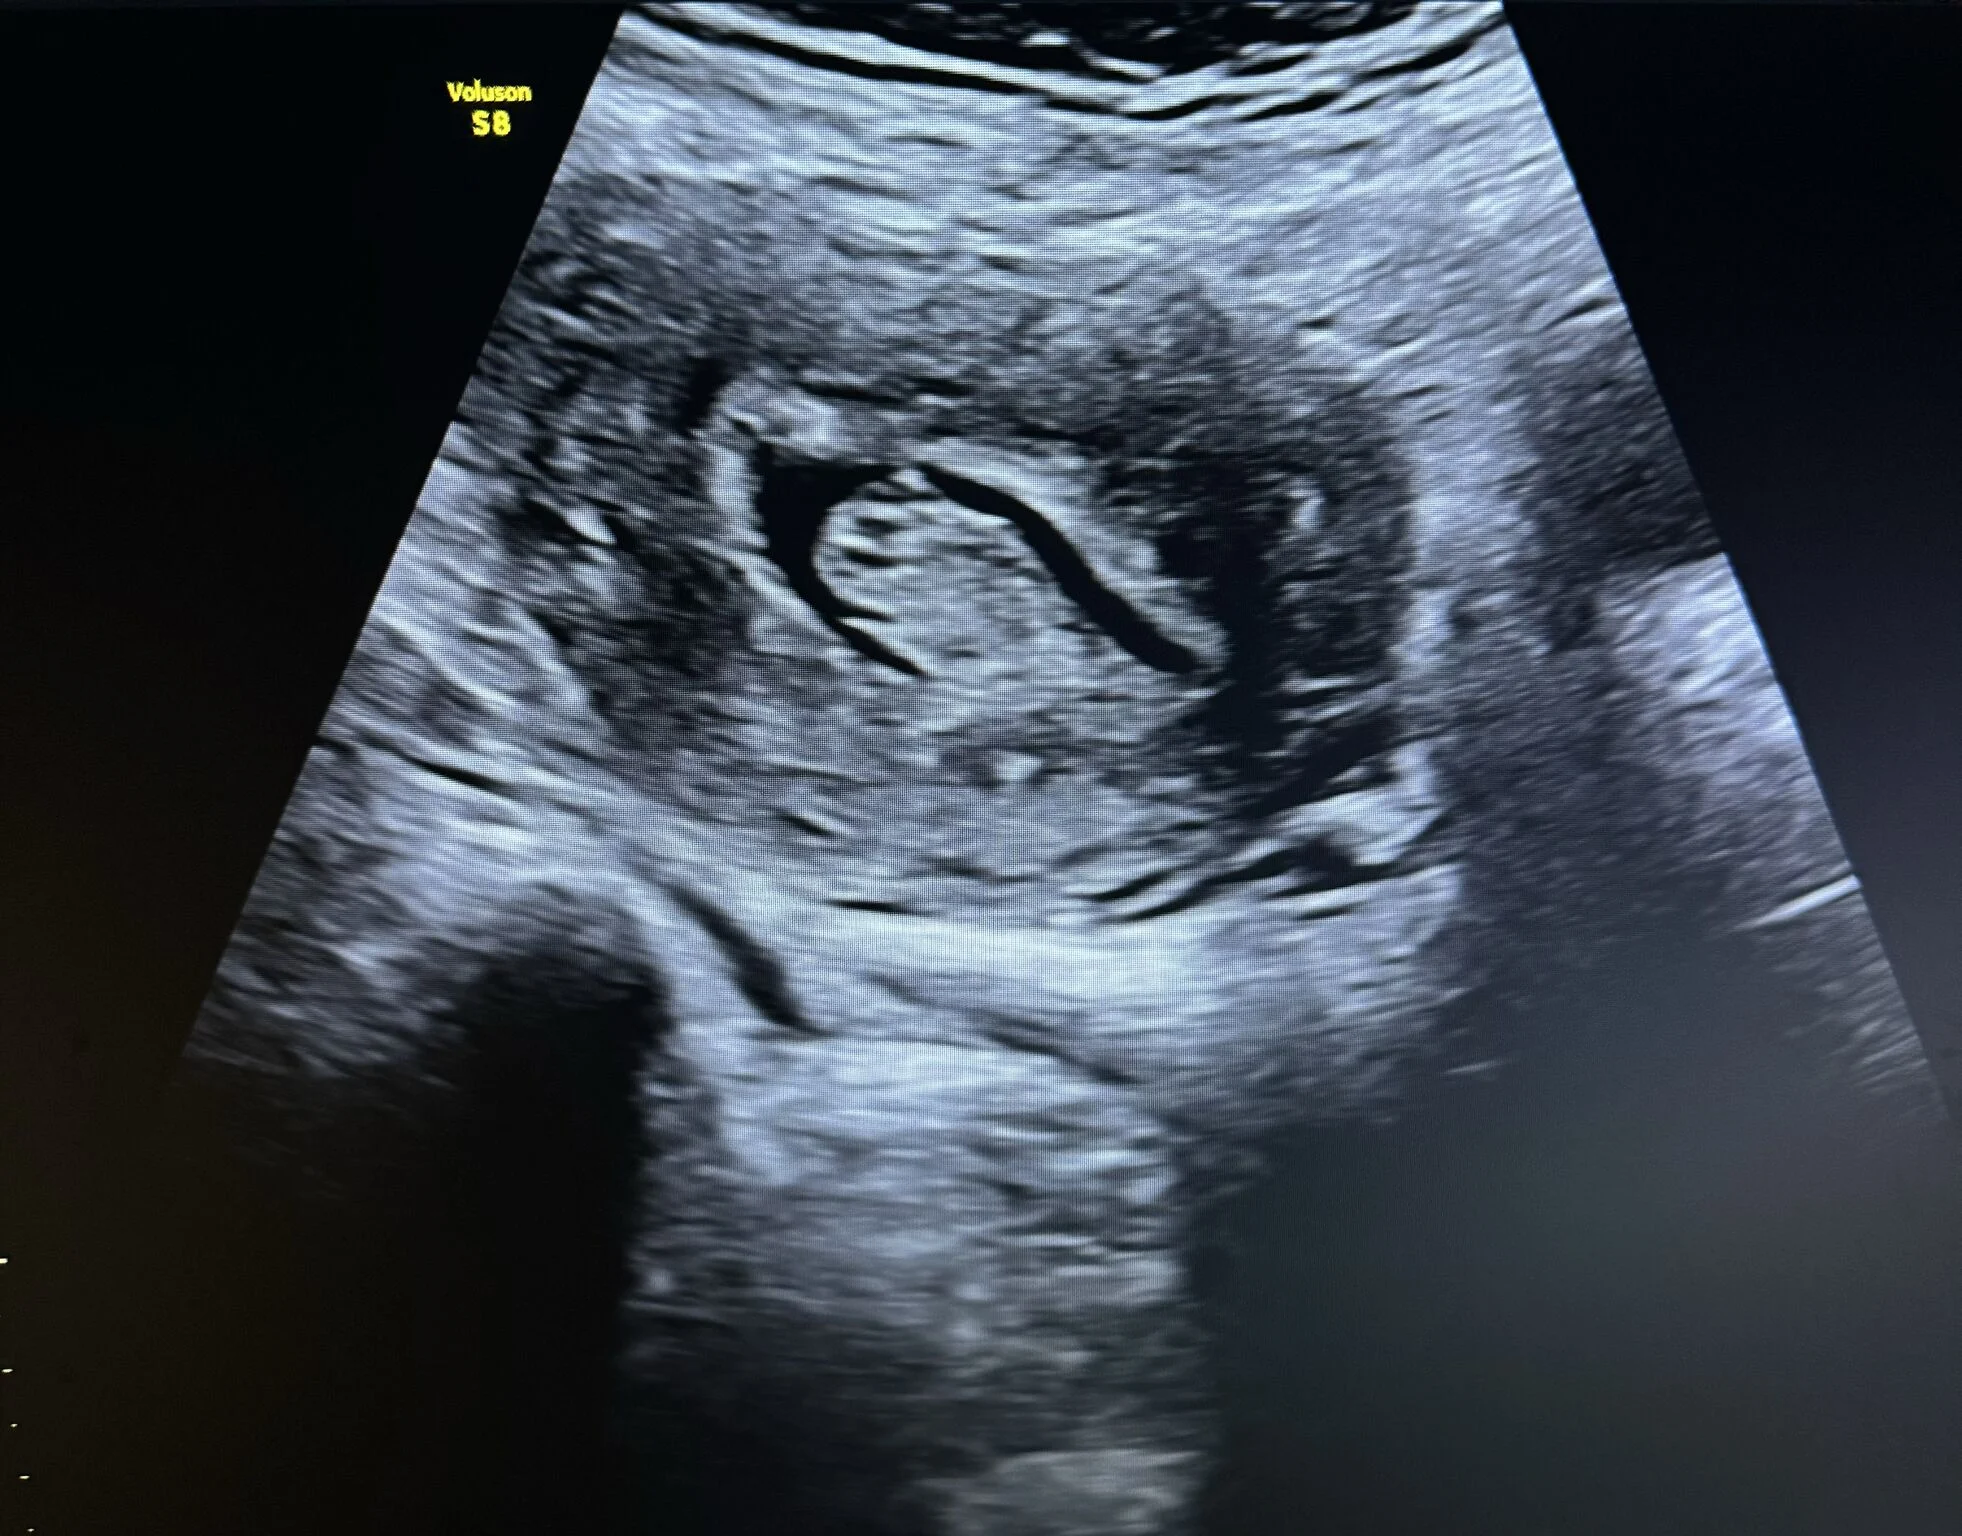

“Case Report: Uterine Polyp

A female patient presented to the clinic with complaints of abnormal uterine bleeding.

Ultrasound examination revealed a large endometrial polyp with notable vascular flow on color Doppler.

Ultrasound Appearance

On ultrasound, an endometrial polyp typically appears as a:

- Well-defined echogenic mass within the endometrial cavity

- Homogeneous texture

- Single central feeding vessel on color Doppler — a key feature distinguishing it from fibroids

Additional features:

- May appear as focal thickening or an oval-shaped lesion

- When using Saline Infusion Sonohysterography (SIS), the polyp can be clearly visualized moving freely within the fluid-filled cavity